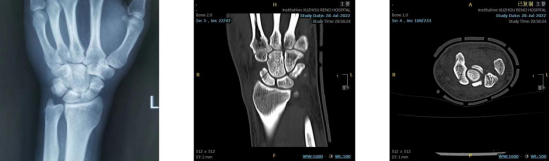

近日,王先生在下楼梯时不慎摔倒,摔倒时他下意识地用左手撑了一下,起身后就发现左手腕开始肿胀、疼痛,在当地医院行X线检查后提示:考虑舟骨骨折,因肿胀疼痛不缓解,为进一步明确诊断、治疗,前往betway在线登陆就诊,经CT检查确诊为左腕舟骨骨折。

术前检查

舟骨骨折是骨科急诊、门诊中较为常见的疾病,其发病率占腕骨骨折的 60%-80%,是腕部骨折中仅次于桡骨远端骨折,多由运动性损伤所致。由于舟骨本身特殊的血供及骨折部位的不同,导致其延迟愈合率、不愈合率和缺血坏死率都很高,尤其对于急性腰部完全骨折和近极骨折,单纯的石膏外固定往往使不愈合率大大增加,并常引发舟骨骨不连、腕关节进行性塌陷(scaphoid nonunion advanced collapse,SNAC)导致腕关节运动功能障碍,因此被称为“令人尴尬但非常重要的小骨头”。由于腕舟骨体积小、解剖结构复杂,三维立体结构特殊,这种手术对医生的要求非常高,如何将Herbert螺钉精准置于舟骨轴线位置是所有骨科医生面临的挑战。